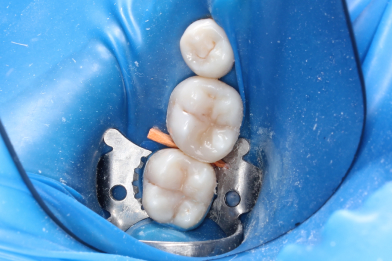

Выполнена изоляция рабочего поля. Под инфильтрационной анестезией раствором Артикаина 1:100000 1,7 мл. Препарирование кариозной полости зуба. Пломба Ceram•X™ светового отверждения. Анатомическая форма зуба и целостность контактного пункта восстановлены

Бояринов Сергей Эдуардович -